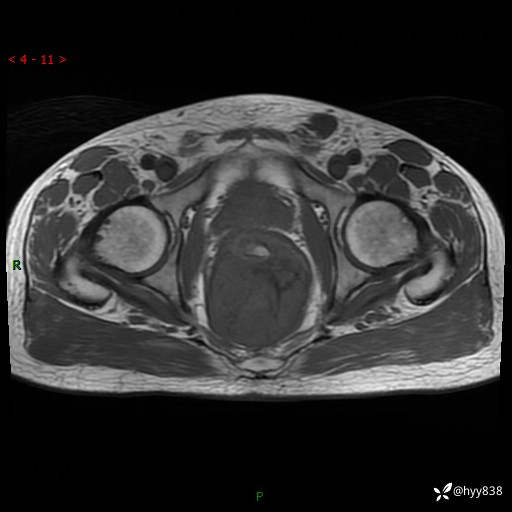

盆腔MRI平扫